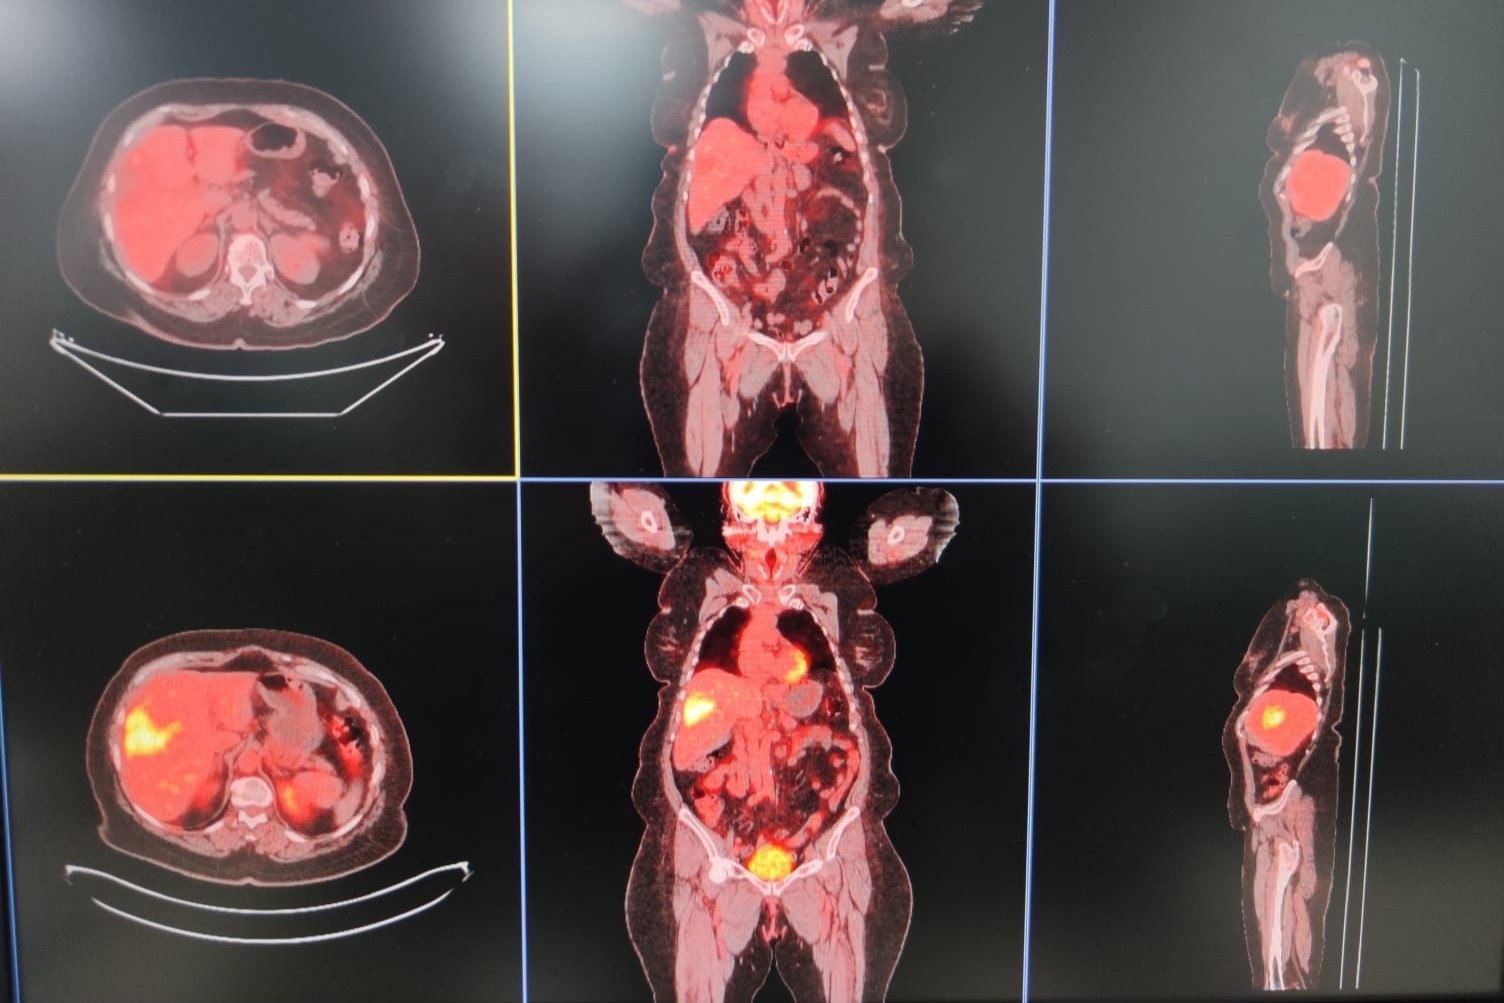

Nükleer tıp birimi ile işbirliği içerisinde hastalara tedavi uyguladıklarını ifade eden Şenol, “Bu servisimizde diğer birimlerle işbirliği yaparak çalışıyoruz. Nükleer tıp en fazla işbirliği yaptığımız birimdir. Hastaların çoğu buraya gelmeden nükleer tıp birimine görünüp öyle bize gelir. Hastanın uygunluğu araştırıldıktan sonra öncesinde burada tedavinin bir provası yapılır.

Kitlenin besleyici damarı bulunup buraya bir prova olarak asıl vereceğimiz ilaca benzer bir ilaçla enjeksiyon yapılıyor. Daha sora nükleer tıp biriminde ilacın o kitleyi ne kadar tuttuğu hesaplanıp uygun dozlarda asıl ilaç dozu hesaplanır.

Bir sonraki seansta aynı şekilde daha önce belirlediğimiz damarın içine girip radyoembolizan dediğimiz küçük parçacıklara radyoaktif maddeler yüklüyoruz.

Biz bu parçacıkları küçük küçük doku içerisine gönderip hem belli bir süre tıkama hem de lokal olarak vücudun diğer taraflarına etki etmeden sadece kitleye etki edip onu öldürme yöntemini kullanarak tümörü tedavi ediyoruz” diye konuştu.